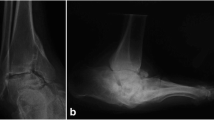

The Charcot foot represents an extreme model for the process linking diabetic neuropathy, osteolysis and vascular calcification. Neuropathy and osteolysis are universal in this condition, and evidence of vascular calcification on plain X-ray has been reported in up to 90%. Vascular dilatation in bone, as reflected in widening of the Haversian canals, has long been recognised to occur in syphilitic osteoarthropathy [35]. However, it is not known why acute Charcot foot should develop in a small subset of patients with diabetic neuropathy. It may reflect the severity of denervation and/or the extent of any associated macrovascular disease, both of which would limit the degree of resultant hyperaemia. But it is also possible that the process is triggered by other factors that exaggerate limb blood flow in a person already predisposed to it by neuropathy. Such factors might include minor trauma, previous foot ulcer and even surgical revascularisation [36]. Such a process would explain the asymmetry observed between affected and non-affected limbs; ipsilateral hyperaemia would be further augmented once any fracture or dislocation occurred in the Charcot foot.